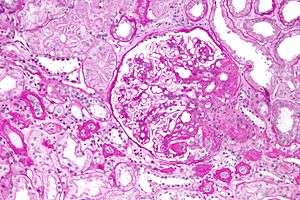

The individual components of the name refer to the appearance of the kidney tissue on biopsy: focal—only some of the glomeruli are involved (as opposed to diffuse), segmental—only part of each glomerulus is involved (as opposed to global),[4] glomerulosclerosis—refers to scarring of the glomerulus (a part of the nephron (the functional unit of the kidney)). The glomerulosclerosis is usually indicated by heavy PAS staining and findings of immunoglobulin M (IgM) and C3-convertase (C3) in the sclerotic segment.[5]

Five mutually exclusive variants of focal segmental glomerulosclerosis may be distinguished by the pathologic findings seen on renal biopsy:[6]

- Collapsing variant

- Glomerular tip lesion variant

- Cellular variant

- Perihilar variant

- Not otherwise specified (NOS) variant.

Recognition of these variants may have prognostic value in individuals with primary focal segmental glomerulosclerosis (i.e. where no underlying cause is identified). The collapsing variant is associated with higher rate of progression to end-stage renal disease, whereas glomerular tip lesion variant has a low rate of progression to end-stage renal disease in most patients. Cellular variant shows similar clinical presentation to collapsing and glomerular tip variant but has intermediate outcomes between these two variants. However, because collapsing and glomerular tip variant show overlapping pathologic features with cellular variant, this intermediate difference in clinical outcomes may reflect a sampling bias in cases of cellular focal segmental glomerulosclerosis (i.e. unsampled collapsing variant or glomerular tip variant). The prognostic significance of perihilar and NOS variants has not yet been determined. The NOS variant is the most common subtype. Collapsingng variant ithesmostmost common type of glomerulopathy caused by HIV infection.